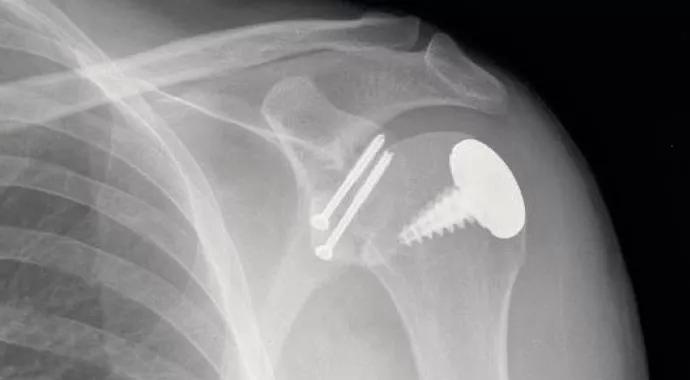

Shoulders with deficient glenoid bone stock also undergo a Latarjet procedure at the same time as humeral defect resurfacing (Figure 2). All operations are performed through a deltopectoral approach, except for one case in which a muscle-splitting technique was used.

Figure 2. Postoperative radiograph of a patient with recurrent shoulder instability treated with a combined Latarjet procedure and a partial cap resurfacing implant for a Hill-Sachs defect